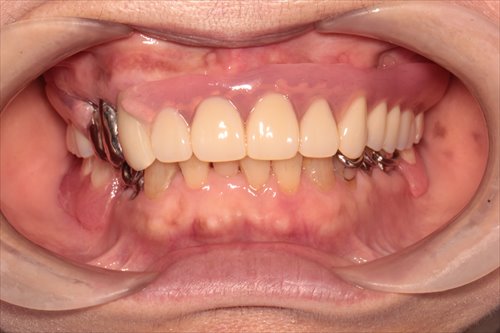

正面観です。

上あごの咬合面観です

咬合面観の解説です。残せる歯は3本しかありません。